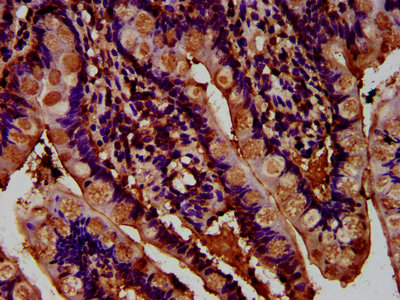

IHC image of CSB-PA812970LA01HU diluted at 1:400 and staining in paraffin-embedded human small intestine tissue performed on a Leica BondTM system. After dewaxing and hydration, antigen retrieval was mediated by high pressure in a citrate buffer (pH 6.0). Section was blocked with 10% normal goat serum 30min at RT. Then primary antibody (1% BSA) was incubated at 4°C overnight. The primary is detected by a biotinylated secondary antibody and visualized using an HRP conjugated SP system.